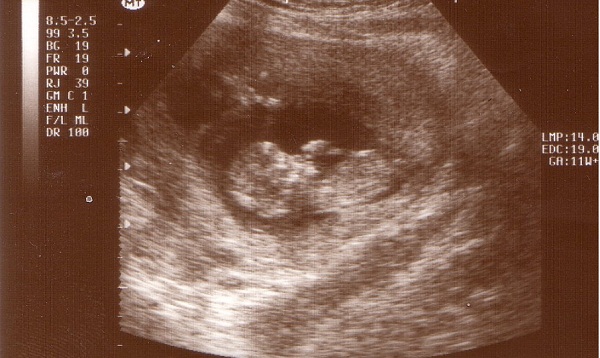

Kép

Krisztonak, Barinak, Csutinak és mindazoknak, akiket nem bántok meg ezzel a fotóval, biztatásul, szeretettel küldöm: Kép

Gratula! Igen! Már látszik a babóca! Nagyon-nagyon szép! Ez a kép a többieknek azt hiszem tényleg biztatásul szolgál majd!

KépKép

Kriszto! Jól emlékszel tényleg ketten vannak, csak a másik mindig elbújik. Nagyon szégyenlős a kicsike. :-) Jelenleg 65 mm-esek, és 2 mm eltérés van a két picúr mérete között! Hétről hétre sokat nőnek önmagukhoz képest.